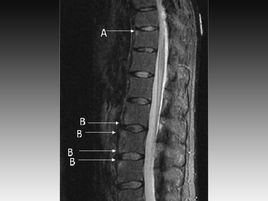

未分化脊柱關節病是指一組具有脊柱關節病的某些臨床和(或)放射學特征,而又表現不典型,但尚未達到已確定的任何一種脊柱關節病診斷標準的疾病。它不是一個獨立的疾病,也不是一種綜合征,它只不過是一組癥狀譜和臨床相的命名,是一個臨時診斷,借以區分類風濕關節炎、彌漫性結締組織病以及其它風濕性疾病。未分化脊柱關節病可以表現為一種或多種癥狀,可間歇出現,可有不同輕重和不同病程。